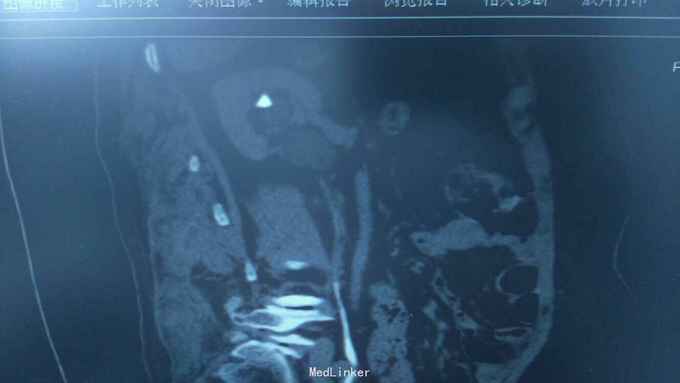

68岁,女性。 主诉:左侧腰痛1年,加重1个月。 病史:1年前无明显诱因出现左侧腰痛,无恶心呕吐,无肉眼血尿。1个月前加重,于外院查泌尿系彩超显示:左肾积液,输尿管显示不清。

诊断:双肾盂旁囊肿 治疗:因患者肾盂未明显受压,疼痛症状不明显,等待观察,暂未予处理。

双侧同时出现的病例并不多见,临床只能通过泌尿系统CTU或增强CT加以鉴别,彩超无法区分肾盂积水及盂旁囊肿。